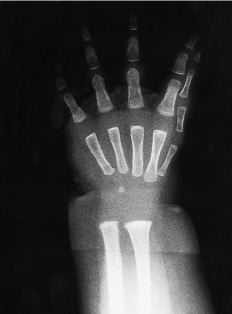

ABFigura 5. Caso 5. A: Mano en espejo típica mostrando los cuatro dedos cubitales de aspecto normal y tres dedos radiales separados por una profunda comisura. B: Imagen radiográfica en que se observa la presencia de dos cúbitos.